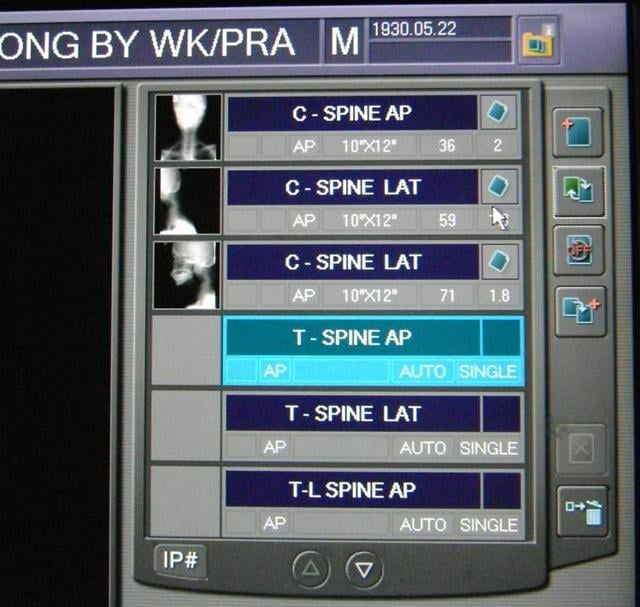

การตรวจเอกซเรย์ ระบบ Digital X-ray และ ระบบประมวลภาพ PAC System ประกายรังสี: QC เอกซเรย์จากแอนะล็อกสู่ดิจิทัล

ประกายรังสี: QC เอกซเรย์จากแอนะล็อกสู่ดิจิทัล 10 ภาพเอกซเรย์แปลกๆ ที่คุณอาจจะยังไม่เคยเห็น